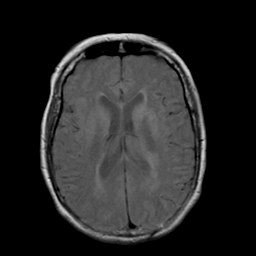

Stroke: proton density-weighted MR #2 -- Slice #14

[Home][Help][Clinical] Slice 14